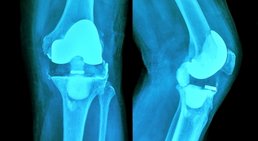

Knieprothese

- Knieprothese

Arthrose, die häufigste aller Gelenkerkrankungen, kann jedes Gelenk betreffen, entwickelt sich jedoch am häufigsten im Knie (Kniearthrose,...